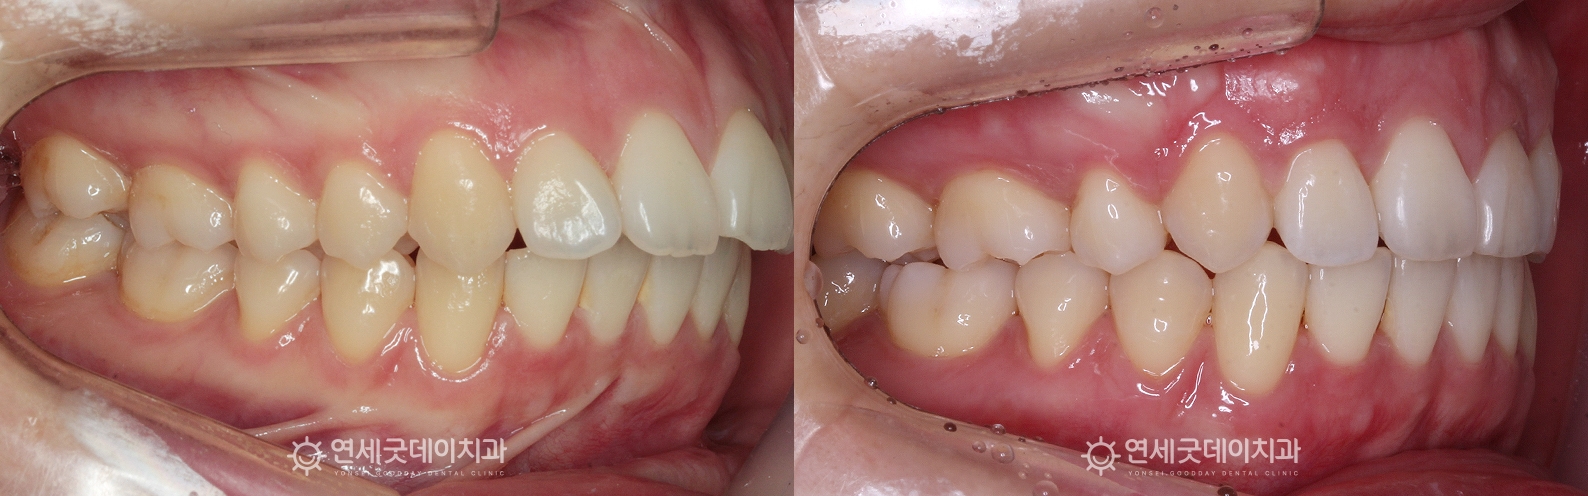

돌출입치아교정 치료전후 (발치, 미니스크류 활용)

돌출입치아교정을 주소로 내원해주신 20대 여성 환자분입니다.

환자분은 잇몸뼈의 돌출이라기 보단, 치아 자체가 앞으로 튀어나온 돌출입 케이스였는데요.

환자분은 상악 #14, 24 두개 치아를 발치하고

약 1년이 경과한 모습입니다.

아랫니 보다 윗니가 다소 돌출되어 있었기 때문에

▲ 돌출입치아교정 종결 (촬영시기 : 2025년 11월)

2년여 간의 발치 교정을 마무리하였습니다.

치아 배열은 물론 뻗쳐있던 앞니 각도가 개선되고

▲ 돌출입치아교정 치료전후 비교